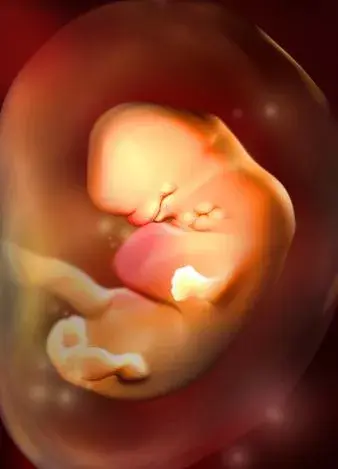

4周:

胎兒只有0.2厘米。受精卵剛完成著床,羊膜腔才形成,體積很小。超聲還看不清妊娠跡象。

5周:

胎兒長到0.4厘米,進入了胚胎期,羊膜腔擴大,原始心血管出現,可有搏動。B超可看見小胎囊,胎囊約占宮腔不到1/4,或可見胎芽。它蘋果籽一樣大小,外觀像個“小海馬”。